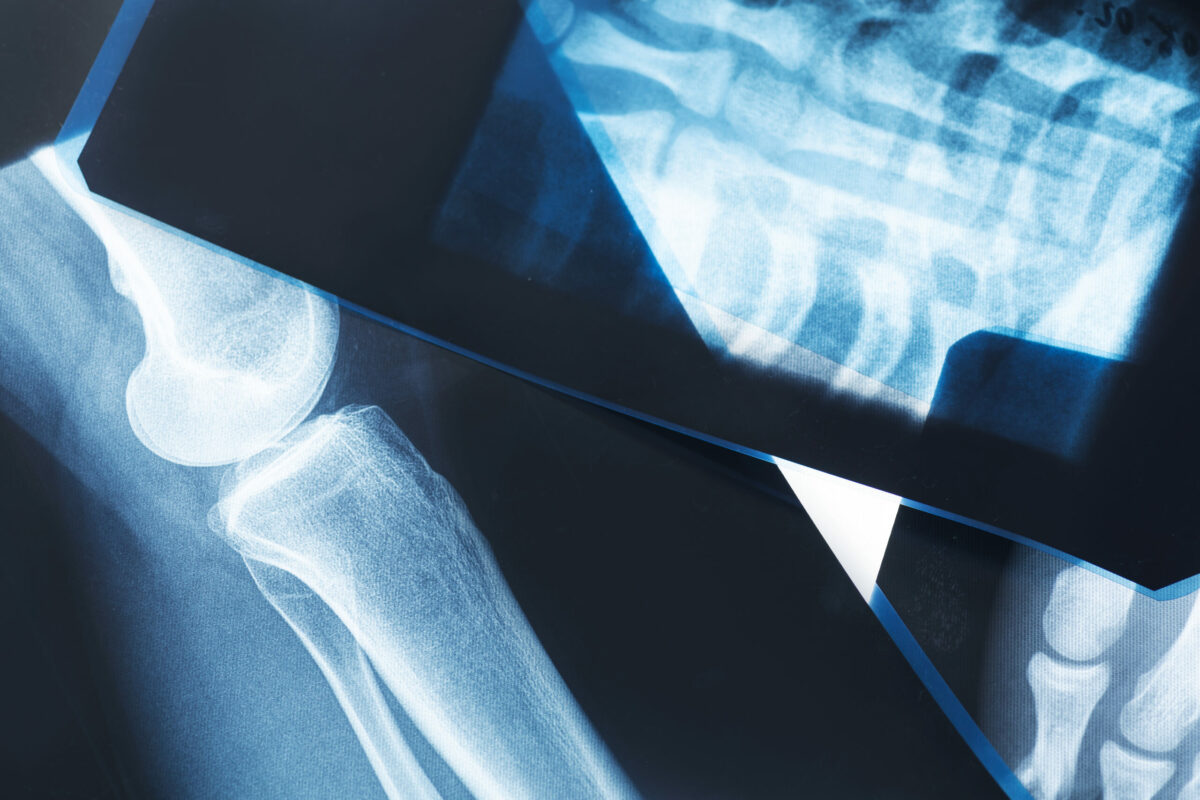

Osteoporosis makes your bones thinner and less dense than usual. In normal circumstances, your bones are strong and dense, which supports your weight and absorbs most impacts. However, as you become older, the density of the bones naturally decreases and they are more fragile. Furthermore, most people do not know they have osteoporosis until they experience a bone fracture. Check below the most commonly affected areas:

A physician can diagnose this health condition with a bone density test. It is an imaging test that helps to measure the strength of your bones and it also uses X-rays to measure calcium and other mineral levels in your bones. In some cases, doctors may refer to DEXA or DXA scans. There are different names but they refer to the same test.

Verifying your bone density is the best way to diagnose osteoporosis and prevent bone fractures.